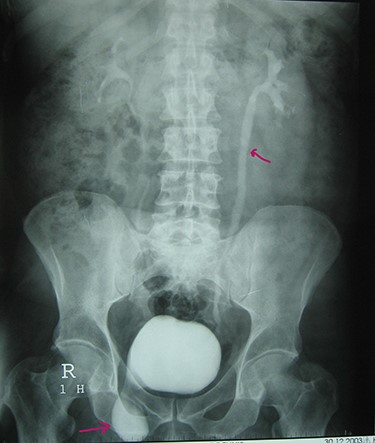

A 72-year-old man with a history of controlled diabetes and hypertension presented to our department with right inguinal swelling and intermittent lower urinary tract symptoms (LUTS) with pollakiuria, dysuria, prolonged micturition time and a sensation of a full bladder after micturition. He reported nausea, vomiting and right lower quadrant paint. The patient also reported having to manually compress the scrotum in order to empty the bladder. Physical examination revealed a slightly painful on palpation and reducible 6 cm right inguinal hernia extending into the right hemiscrotum. The body mass index of the patient was 31.4 kg/m2. His PSA was 4.3 ng/ml. On uroflowmetry, maximum flow rate (Qmax) was 13 ml/s and the voided volume was 180 cc. The uroflow curve was flat. The Bacteriological examination of urine was negative. Retrograde urethrocystography revealed right inguinal hernia containing a portion of the urinary bladder (Figs 1,2). He also had an intravenous urography in order to study the upper urinary tract and to have an idea of the renal function. This radiological exploration confirms the data of the retrograde urethrocystography and illustrates well the bladder hernia. However, a moderate left hydronephrosis with a nonobstructive pyelic calculus of 1.5 cm was observed on intravenous urography (Figs 3,4). Intraoperative findings revealed a direct right inguinal hernia with complete herniation of bladder into the scrotum. The bladder appeared healthy with no signs of injury and was restored to its normal anatomical position without resection. The hernia was repaired with a biologic mesh by the Lichtenstein technique. The patient had an uneventful postoperative course. Concerning his pyelic calculus problem, shock wave lithotripsy sessions were scheduled.

Retrograde urethrocystography: right inguinal hernia containing a portion of the urinary bladder.